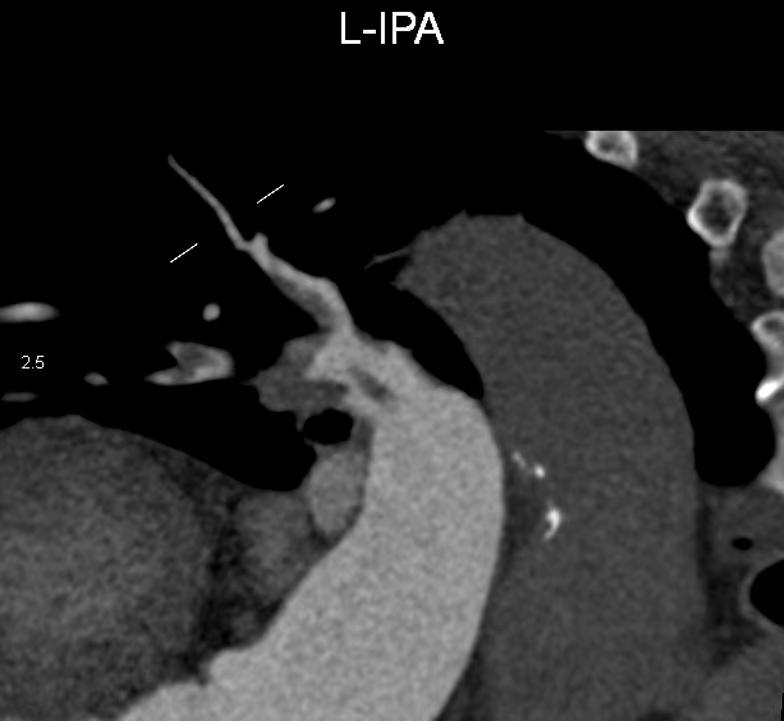

结合患者病情特点,医生决定立刻给予朱阿婆溶栓治疗,治疗后其左肺动脉栓塞较前基本吸收,右肺动脉栓塞较前部分吸收,病症明显改善,检查相较于治疗前明显好转。